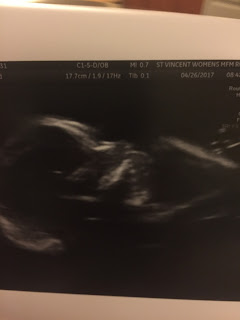

Best moment this week: We got to see our nugget at my 20 week u/s. I was super nervous for this and didn't sleep well. I might have a little PTSD. But all is good, I met a new MFM MD and he was good. The babe was in a funky position and we couldn't get a good picture of the heart and spine and he felt given my history we would all feel better getting a better look in a month. So we are praying there is nothing wrong. But i have to say I'm grateful for him being so conservative. He said that although he wasn't worried about this babe at all he felt we would all feel better knowing for certain. I don't know why this touched me. I felt like even though he wasn't even the slightest bit involved with our care last time (he wasn't part of the group then) he cared. He cared enough to put these nervous parents at ease. I'm grateful to that.

Gender: I still think girl, even though this feels the most like Lando. at our u/s Adam swears the tech said the gender but I didn't hear it. It was after she had scanned gender area and I guess she used a pro-noun and he swears that it was the one of the baby, but I myself always use a pronoun and it isn't always right. Although the MD looks at the scans in the room and I swear he clicked on the picture of the gender, but I quickly turned my head....